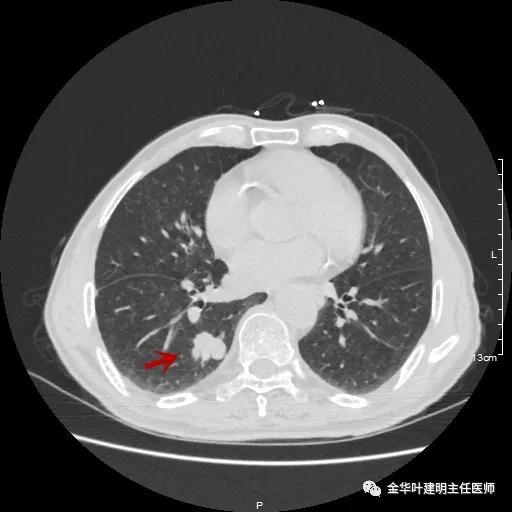

以上示右下叶病灶5。也是主病灶,是实性块状分叶的占位性病变,基本可以肯定是肺癌。单病灶看需下叶切除并清扫淋巴结。

以上示右下叶病灶6。同样是囊腔型病灶,但较前几个范围小,可囊壁同样为磨玻璃影,也是较为典型的囊腔型肺癌表现,单灶来看可下叶背段切除。